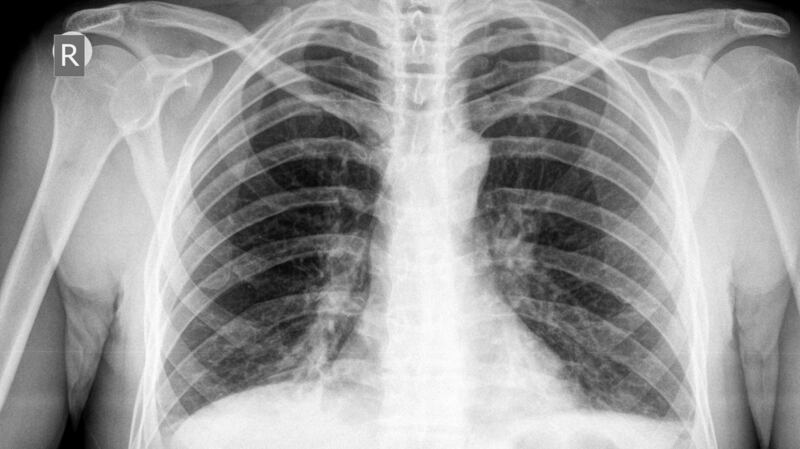

“Considering the infection is in the lungs, the inhaler means the medication can target the disease directly,” said Prof Cryan, associate professor of pharmaceutics in RCSI’s school of pharmacy and the senior author of the study.

The treatment is administered through an inhaler, and reduces the lung bacteria that causes tuberculosis while helping patients’ immune systems to fight the disease, the researchers have said. However, the inhaler has thus far only been used on mice.